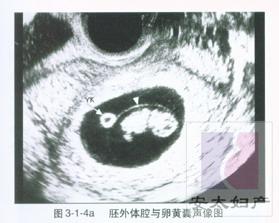

怀孕两个月指妊娠的5~8周。 在此时期,胎儿的成长满7周时,胚胎身长约2.5厘米,体重约4克。心、胃、肠、肝等内脏及脑部开始分化,手、足、眼、口、耳等器官已形成,已越来越接近人的形体。绒毛膜更发达,胎盘形成、脐带出现,母体与胎儿的联系非常密切。

怀孕2个月胎儿b超图片:{点击此处进入胎儿图片集}